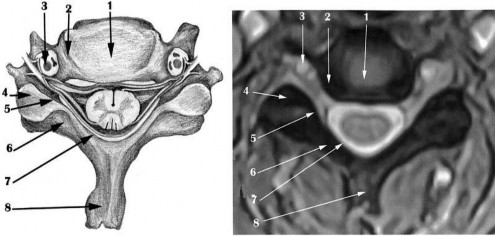

Hình 1.5. Mô hình cắt ngang cột sống cổ (hình trái) và hình ảnh MRI cắt ngang cột sống cổ C4 - C5 ở một thanh niên bình thường (hình phải)

Ảnh T2W thấy: (1) nhân nhầy tăng tín hiệu màu trắng đồng nhất do có nhiều nước. (2) vòng sợi giảm tín hiệu có màu đen, chu vi vòng sợi đều sắc nét. (3) động

mạch đốt sống. (4) diện khớp liên mấu. (5) rễ thần kinh. (6) cung sau đốt sống. (7) dây chằng vàng. (8) gai sau thân đốt.